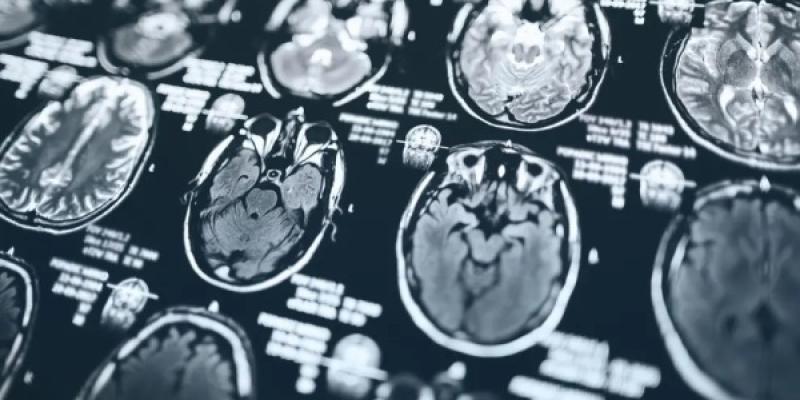

Recientemente, un estudio publicado en Cell Reports ha encontrado una posible conexión entre el virus del herpes simple (HSV-1) y el Alzheimer. El HSV-1 es el causante más común de infecciones en la boca, labios, cara o genitales. Según la investigación, el ADN del virus contiene proteínas que, al parecer, están involucradas en el desarrollo de la enfermedad de Alzheimer. Los investigadores analizaron muestras post-mortem de tejido cerebral de pacientes con Alzheimer y encontraron que las proteínas del herpes estaban presentes en las mismas áreas cerebrales que los depósitos anormales de proteína tau, una característica patológica clásica de este tipo de demencia.

Este hallazgo abre nuevas posibilidades para el desarrollo de tratamientos contra enfermedades neurodegenerativas. Los investigadores sugieren que entender cómo la proteína tau interactúa con las infecciones virales podría llevar a estrategias para proteger el cerebro de los efectos del herpes y otras infecciones virales que podrían contribuir a enfermedades neurodegenerativas. De hecho, experimentos realizados en organoides cerebrales (pequeños "órganos" creados en laboratorio a partir de células humanas) mostraron que la infección por HSV-1 aumentaba la cantidad de proteína tau anormal. Sin embargo, la proteína tau alterada parecía reducir la cantidad de proteínas virales, lo que podría implicar una respuesta inmune natural del cerebro ante infecciones virales.